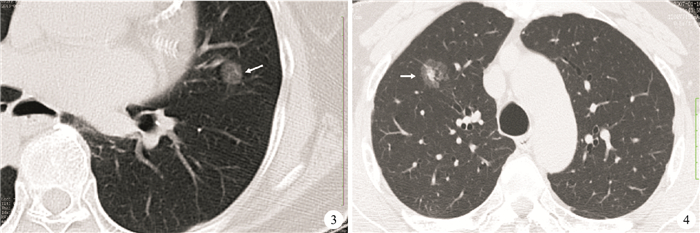

CT篩查肺癌的應用增加導致早期病變的識別增加,如原位腺癌(adenocarcinoma in situ,AIS,病理大小≤30 mm,非浸潤性伏壁樣生長,CT上通常為非實性;圖 3)和微浸潤腺癌(minimally invasive adenocarcinoma MIA,病理大小≤30 mm,浸潤在5 mm或以下的伏壁樣生長為主,CT上大體為非實性組織,但可能含近5 mm的中央實性成分;圖 4)[22]。這些病變不應視作常見的侵襲性腺癌,可采取隨訪觀察而非手術切除[22]。